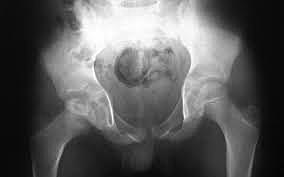

John Rhea Barton (1794-1871) realizó una osteotomía subtrocantérea del fémur por una severa deformidad en flexión-aducción de la cadera. Se le conoce sobre todo por sus innovadoras osteotomías correctoras para articulaciones anquilosadas.

Jacques Calve (1875-1954) de Berck, Francia, Arthur T. Legg (1874-1939) de Boston, EEUU y George Perthes de Tubingen, Alemania, describieron la enfermedad de Perthes. De ahí que dicha enfermedad sea denominada en ocasiones enfermedad de Calve-Legg-Perthes. Con la ayuda de radiografías, Calvé comprobó que algunos casos de caderas tuberculosas en niños eran en realidad casos de coxa plana.